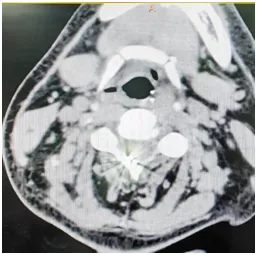

▲ 二期高颈段2根刺激电极及神经刺激器永久植入后正侧位透视

▲ 术后复查CT,电极位置正常

经历1个月的短时程脊髓电刺激及综合治疗,患者疗效确切昏迷评分及脑电图意识分级较前均提高,寿记新主任指出:该患者已行多次颅脑手术,二期脊髓电刺激手术一定要创伤最小化,可选择穿刺技术将两根电极线植入高颈段。2025年1月7日,在复合手术室,寿记新主任医师主刀,在王建业副主任医师、管海博医师、屈罡生麻醉医师、孙楹电生理监测医师、郭瑜护师共同努力下,顺利完成了二期脊髓神经刺激电极及刺激器植入术,此手术方式比起颈后部开刀打开椎板植入外科电极,创伤小、手术时间短、可提前刺激器开机,更易被家属接受,为患者尽早拔除气管套管、意识恢复奠定了良好基础。

术后3天神经刺激器已顺利开机,患者耐受性良好、可睁眼、临床症状逐渐好转,患者家属倍感欣慰,目前患者仍在继续接受团队的综合治疗。